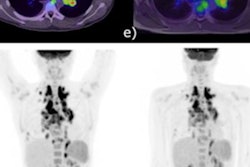

Also, neuro-oncologists use PET/MRI to monitor patients undergoing treatment, primarily to identify glioblastomas that may have returned after surgical removal. Umutlu showed an example of such a case in which MRI alone would probably have missed a tumor, but that was clearly shown with the addition of PET.

The PET component of PET/MRI can reveal brain tumors that may go undetected by MRI alone."This was one of the cases where the PET component really helped us make a clear diagnosis in terms of a second manifestation of a brain tumor," she said.